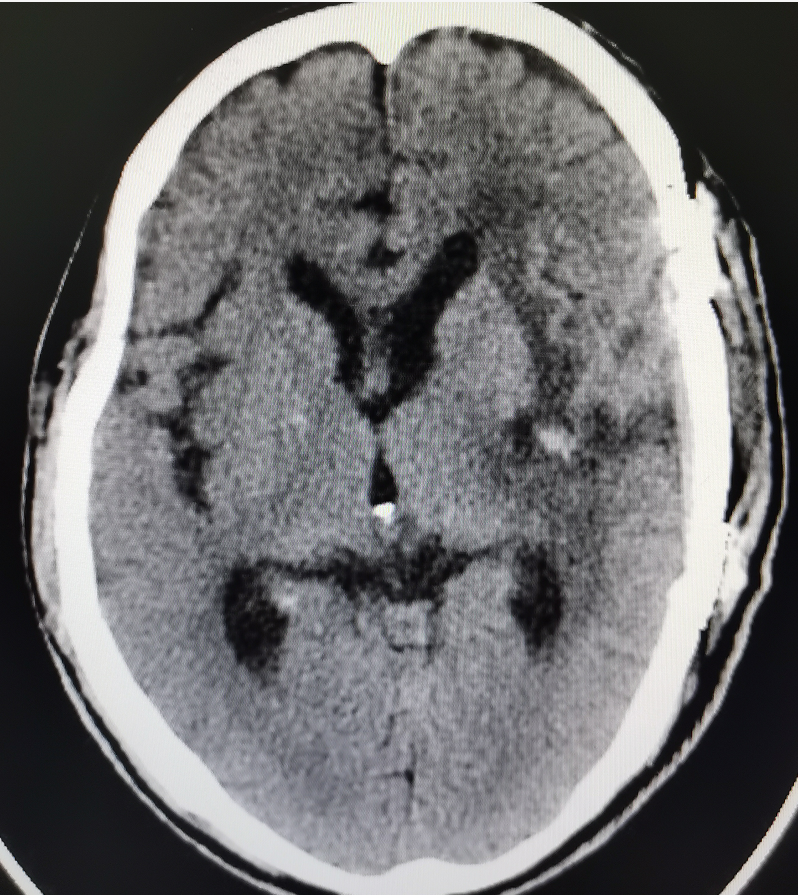

据术后复查颅脑CT(图3)结果显示,巨大的脑肿瘤已全部切除,瘤腔无渗血。术后患者意识、肢体功能、言语等情况均大幅度的好转,极大提高了病人的生活质量。

图3.术后影像资料,肿瘤被完全切除,脑室恢复,中线回位,脑水肿好转